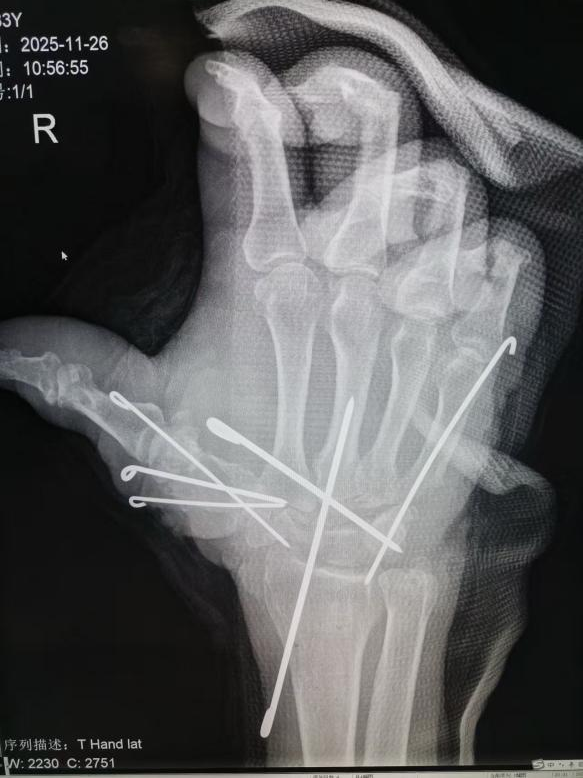

手术全程在高倍显微镜下进行。医院创伤手外科主任黄大波带领医疗团队,凭借精湛的显微外科技术,精准吻合断裂的微小血管,细致修复受损的神经与肌腱,同时采用克氏针对骨折部位进行牢固固定,一步步为老人重建手掌的血运、神经及骨骼支撑结构。7个小时里,团队全程坚守岗位、不敢有丝毫懈怠。最终,这场毫厘之间的“修复战役”顺利完成。